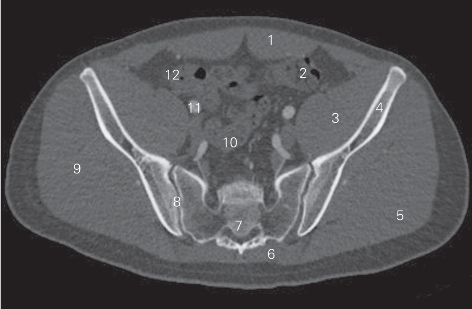

图5-1 经骶髂关节的横断层CT图像(骨窗)

1 腹直肌 rectus abdominis 2 乙状结肠 sigmoid colon

3 髂肌 iliacus 4 髂骨翼 ala of ilium

5 臀大肌 gluteus maximus 6 竖脊肌 erector spinae

7 第3骶椎 3rd sacral vertebrae 8 骶髂关节 sacroiliac joint

9 臀中肌 gluteus medius 10 直肠 rectum

11 髂外动脉 external iliac artery 12 盲肠 cecum